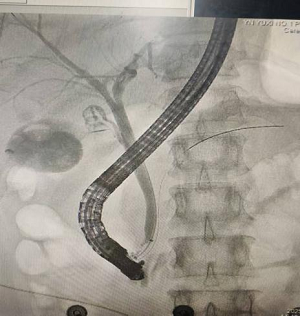

术中影像